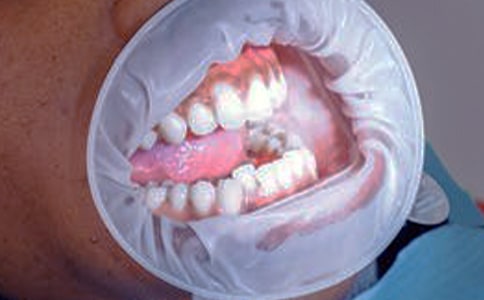

牙齦炎出現(xiàn)牙齦炎時,表現(xiàn)為牙齦發(fā)紅、腫大、松軟、發(fā)亮、容易出血,尤其是刷牙、吃東西等刺激后出血更明顯,部分患者還會出現(xiàn)牙齦疼痛,到了第八個月時隨激素分泌濃度增高變得較為嚴(yán)重。

妊娠瘤個別孕婦會出現(xiàn)更為嚴(yán)重的牙齦損害——妊娠瘤,它是懷孕期間牙齦組織出現(xiàn)的良性增生,一般多在懷孕后二、三個月時出現(xiàn),但也可以更晚一些才出現(xiàn)。

妊娠瘤表現(xiàn)為前排兩個相鄰牙齒間的牙齦尖端,出現(xiàn)紫紅色或暗紫色的腫塊,腫塊呈蒂狀或結(jié)節(jié)狀,表面平滑柔軟,腫塊比較大時可擋住部分牙齒妊娠瘤除了外觀特點(diǎn)以外,還會出現(xiàn)感覺不舒服、影響說話、吃飯、經(jīng)常出血,有時還會出現(xiàn)疼痛。